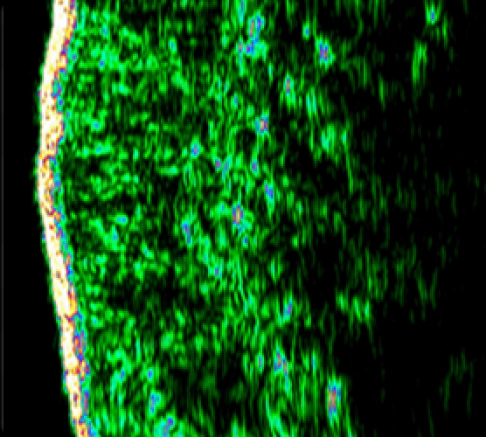

Skin Changes after Rejuran Healer treatment

Skin density and thickness before rejuran.

Skin density and dermal layer thickness

before treatment

Skin density and thickness after Rejuran.

Doubled skin density and dermal

layer thickness

Rejuran Healer experiment results

By increasing the density and thickness of the dermis, the skin barrier is healthier.

It promotes overall healthy skin and natural elasticity.